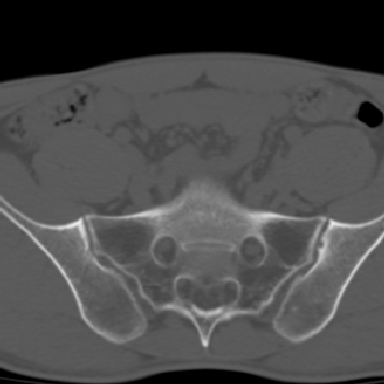

m 30 腰背部不适半年; 清晨时僵硬; 活动症状有所改善

双侧骶髂关节下2/3关节面模糊,毛糙,可见小囊状骨质破坏区.支持强直性脊柱炎.

强直性脊柱炎的早期改变!不仅表现为双侧骶髂关节,第5腰椎与骶椎间的关节突关节也有类似改变。

双侧骶髂关节下2/3关节面模糊,毛糙,髂骨侧可见小囊状骨质破坏区,骶髂关节间隙增宽(软骨破坏期)。支持早期强直性脊柱炎。

双侧骶髂关节下2/3关节面模糊、毛糙,可见小囊状骨质破坏区,呈虫咬状改变,周围可见增生硬化.支持强直性脊柱炎早期表现.

双侧骶髂关节髂骨面硬化,毛糙,小囊变,属于早期强直性脊柱炎